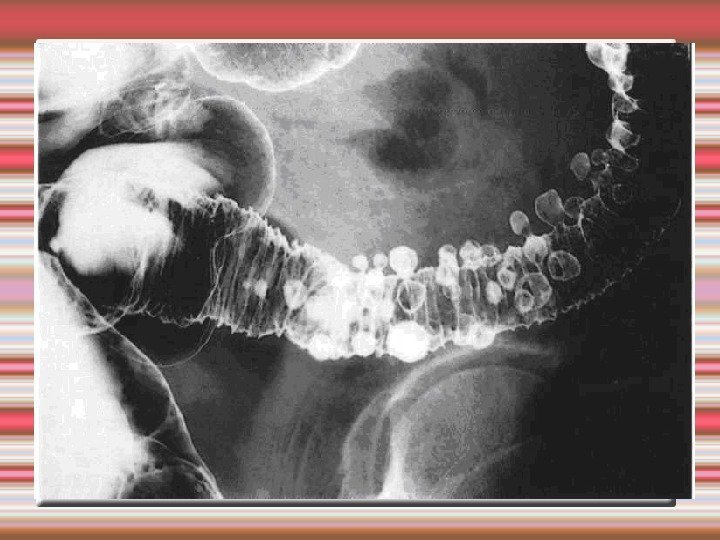

Диагностика дивертикулеза толстой кишки Жалобы и анамнез Ирригоскопия Фиброколоноскопия

Ирригография дивертикулез толстой кишки